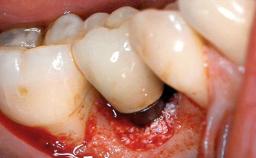

Peripheral Giant-cell Granuloma Associated with Peri-implant Tissues

Giant-cell granulomas (GCG) of the jaws are benign reactive lesions of unknown etiology, unrelated to giant-cell tumors (osteoclastomas), which are defined as benign but locally destructive and aggressive neoplasms (Jundt and coworkers 2005). Depending on their localization at the initial diagnosis, GCG are dived into central (CGCG) and peripheral (PGCG) types. CGCGs occur within the jawbones and appear as unilocular or multilocular radiolucent lesions. The incidence in the general population is very low. They are more commonly found in the mandible, mainly in children and young adults—patients are generally younger than 30 years—and have a greater incidence in females (Heithersay and coworkers 2002). The clinical behavior of CGCGs varies from slowly growing asymptomatic swellings to aggressive lesions that may result in pain, cortical perforation of the affected jaw site, and root resorption (de Lange and coworkers 2007).